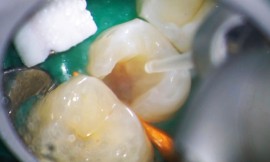

Les lésions endodontiques : décision thérapeutique S’entourer du maximum d’éléments de bonne qualité (imagerie 2D, 3D, rétro-alvéolaires) est le premier conseil avant d’envisager un projet endodontique qui peut aboutir à des résultats spectaculaires comme l’ont montré les cas cliniques présentés par Jean-Yves Cochet.

Les lésions endodontiques : décision thérapeutique

Durée : 4:44 S’entourer du maximum d’éléments de bonne qualité (imagerie 2D, 3D, rétro-alvéolaires) est le premier conseil…